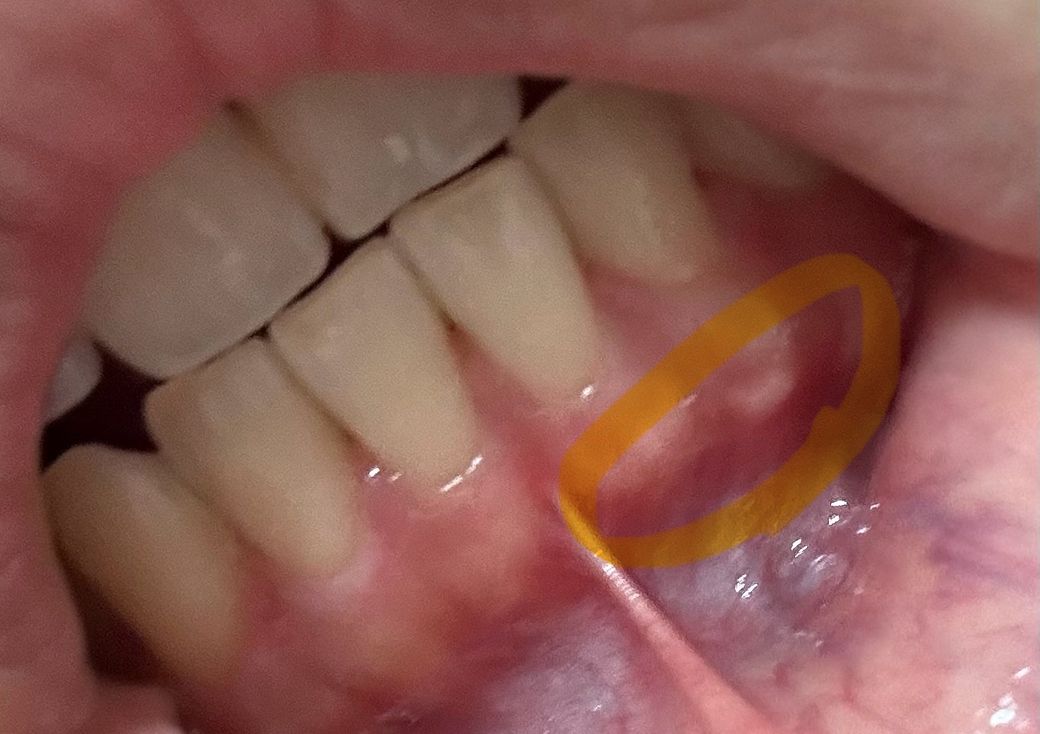

잇몸이 하얗게 올라왔는데 뭘까요 ㅠㅠ

잇몸에 하얗게 올라왔습니다..

심각한거일까요 ..?

단순 구내염일까요 염증일까요

피는 안납니다

가만히 잇으면 아프진 않고 누르면 아픕니다..

사진에 보이는 부분은 잇몸뼈가 잇는곳이 상대적으로 잇몸이 얇아서 보이는 부분입니다. 문제가 잇는건 아닙니다.

사진이 흐려 명확한 진단을 하기엔 어렵지만 단순한 구내염일 가능성이 높아보이며 며칠 지나보셔야겠습니다.

말씀하신 부분에 대한 사진이 명확하지 않아 판단하는데 있어 어려움이 있습니다. 다만 사진을 유추했을 때 구내염이거나 치아 뿌리가 비쳐 보일 가능성이 있습니다. 특히 아래쪽 사진은 치아 뿌리가 잇몸을 늘리면서 비쳐 보인다고 보시면 됩니다. 위쪽 사진에서의 부위가 통증이나 불편감이 있다면 치과 방문 후 검사를 한 번 받아보시길 바랍니다.

현재 구내염이 생긴것으로 보이며, 일부러 건드리거나 하지는 말고 염증이 가라앉을수 있도록 소독용 헥사메딘 가글액으로 가글하여 관리하여 주길 권합니다. 만약 크기가 커지고 통증이 심해지는 경우에는 치과 진료를 받길 권합니다.